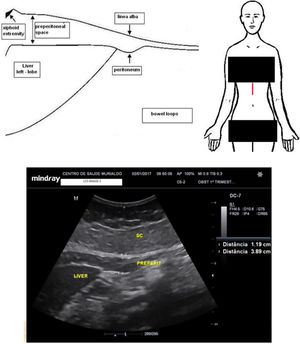

Maternal epigastric fat evaluationMaternal epigastric fat tissue was assessed with a convex probe placed in the middle sagittal epigastric region aiming to measure the visceral and subcutaneous tissues using a method adapted from the studies by Suzuki et al.17 Attention was paid to avoiding excessive pressure that could falsely compress the surfaces of interest. The ultrasound calliper was placed spanning from the deepest anterior liver surface to the linea alba to assess the epigastric maternal visceral adipose tissue (epigastric m-VAT). Thereafter the electronic calliper was moved to span from the linea alba to the superficial dermal edge to determine the epigastric maternal subcutaneous adipose tissue (epigastric m-SAT). Fig. 1 shows the ultrasound measurements